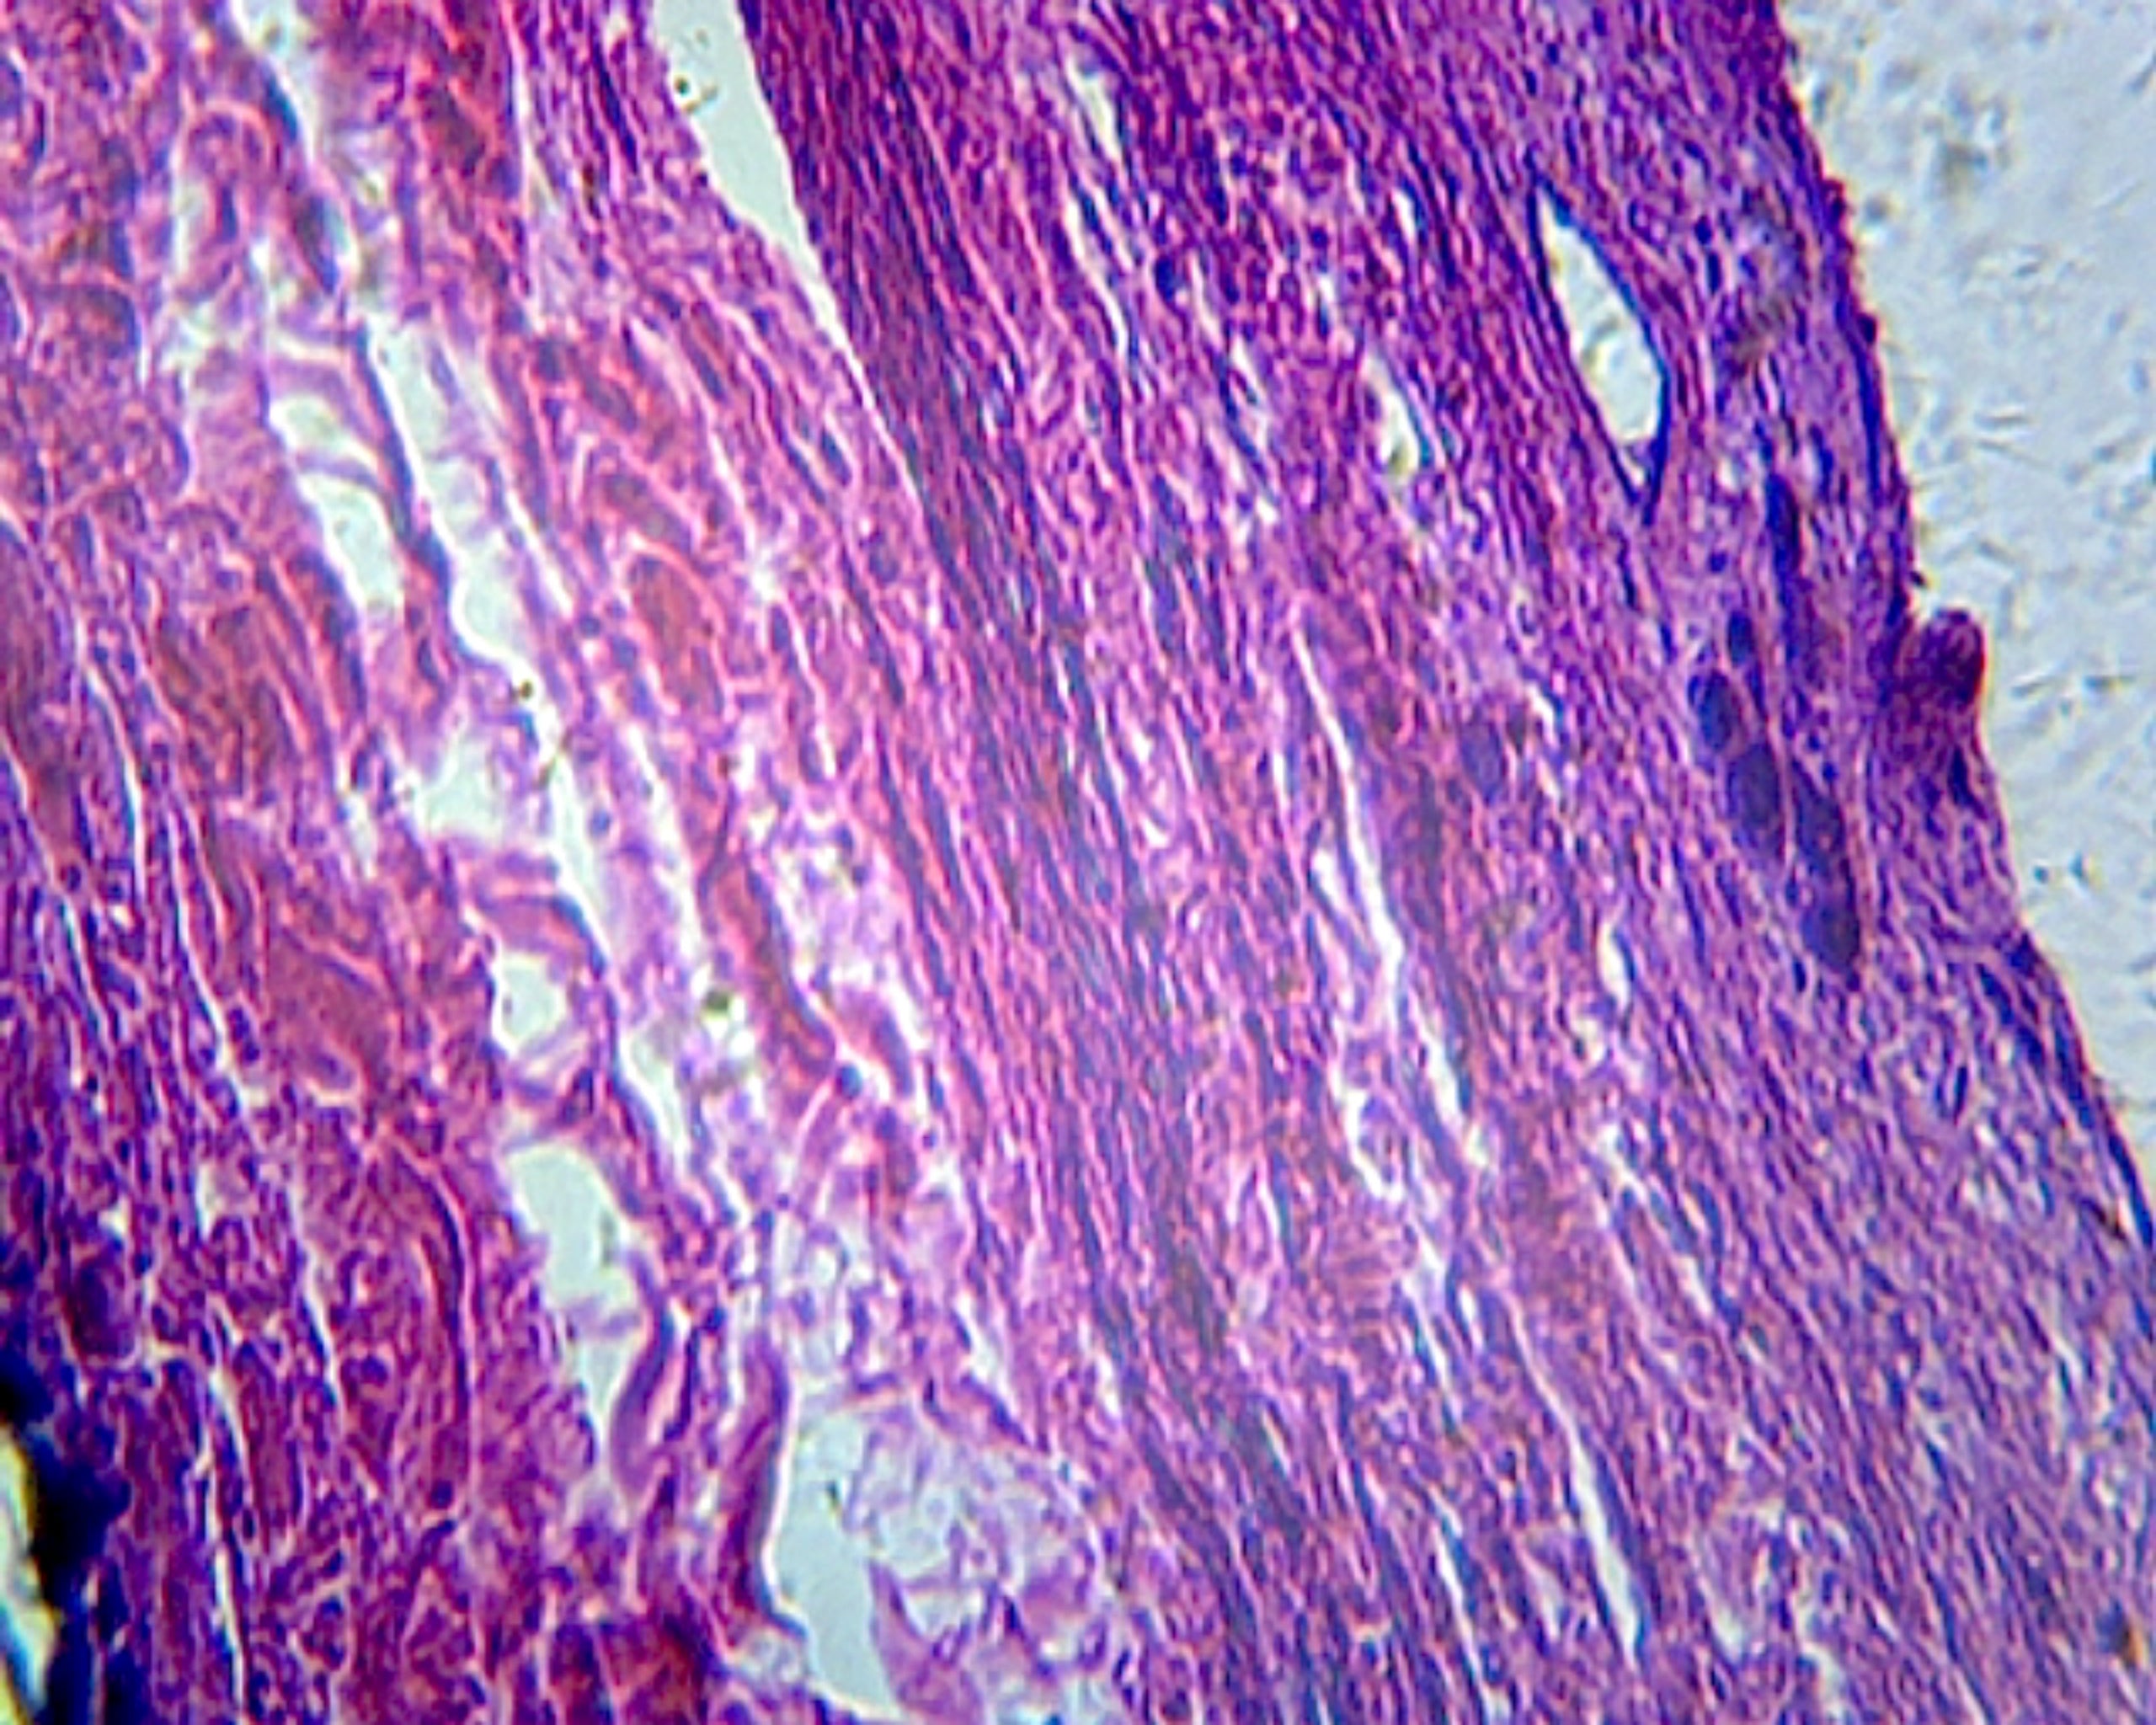

This slide is a section of a gallbladder from a mammal showing simple columnar epithelium, serosa, and the muscular layer.